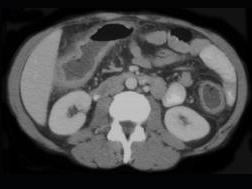

问题 女,40岁,腹痛、腹泻、脓血便、里急后重,结合图像,选择最可能诊断 ( )

选项 A、慢性溃疡性肠炎 B、结肠淋巴瘤 C、结肠克罗恩病 D、结肠结核 E、假膜性肠炎

答案 A